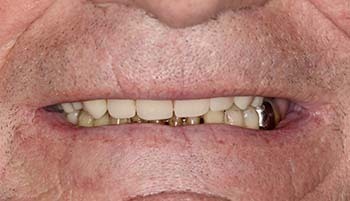

Aspect du bridge provisoire juste avant de confectionner le bridge d‘usage.